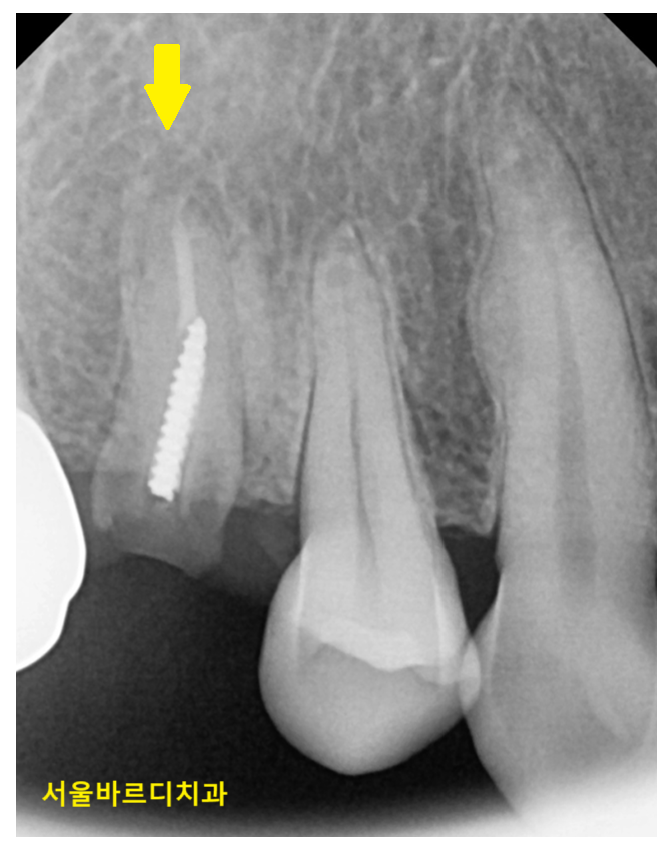

사진을 보시면 아시겠지만 뿌리만 남은 경우입니다.

거의 잇몸에 박혀있죠.

x-ray를 찍어 확인해보니 신경치료도 되어있고

우식이 심했었는지

치아에 기둥까지 박혀있습니다.

씌운 치아 부러짐이 발생한 것인데..